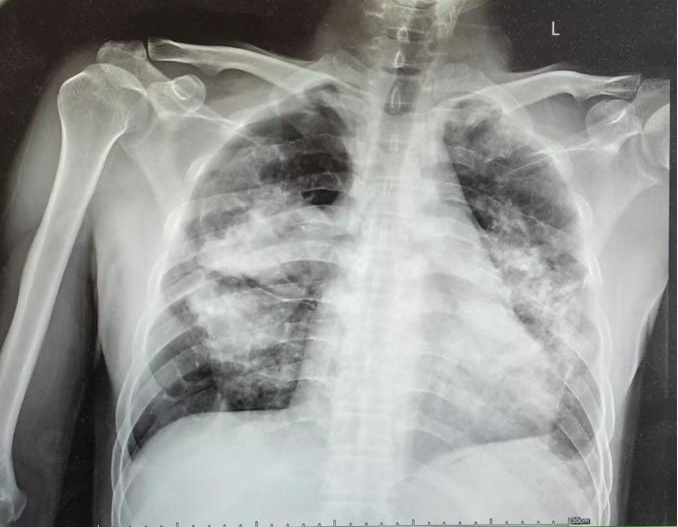

入院检查,发现王先生吸氧时血氧饱和度90%以下。胸部CT检查显示右侧气胸,两肺多发斑片、结节及团片影,左肺肺大疱,肺动脉增宽,纵膈及双侧肺门淋巴结增大,诊断为终末期尘肺,如果不立即进行治疗,患者极有可能因呼吸衰竭而死亡。肺移植手术成为唯一且有效的治疗手段。

患者术前胸部影像